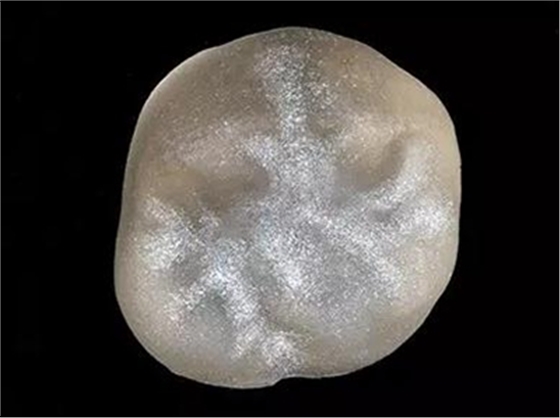

步驟1 原始狀況

16牙位牙齒牙合面觀.

牙齒經(jīng)過(guò)根管治療且充填修補(bǔ),需要重新修復(fù)。